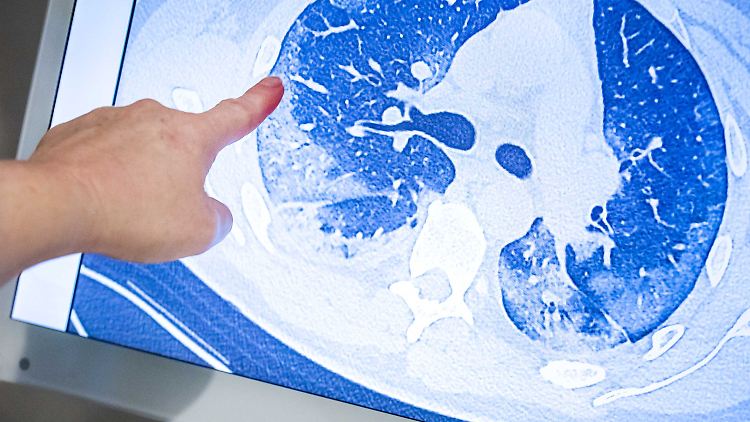

Die Computertomografie zeigt die Lunge eines Covid-19-Patienten.

(Foto: picture alliance/dpa/ANP)